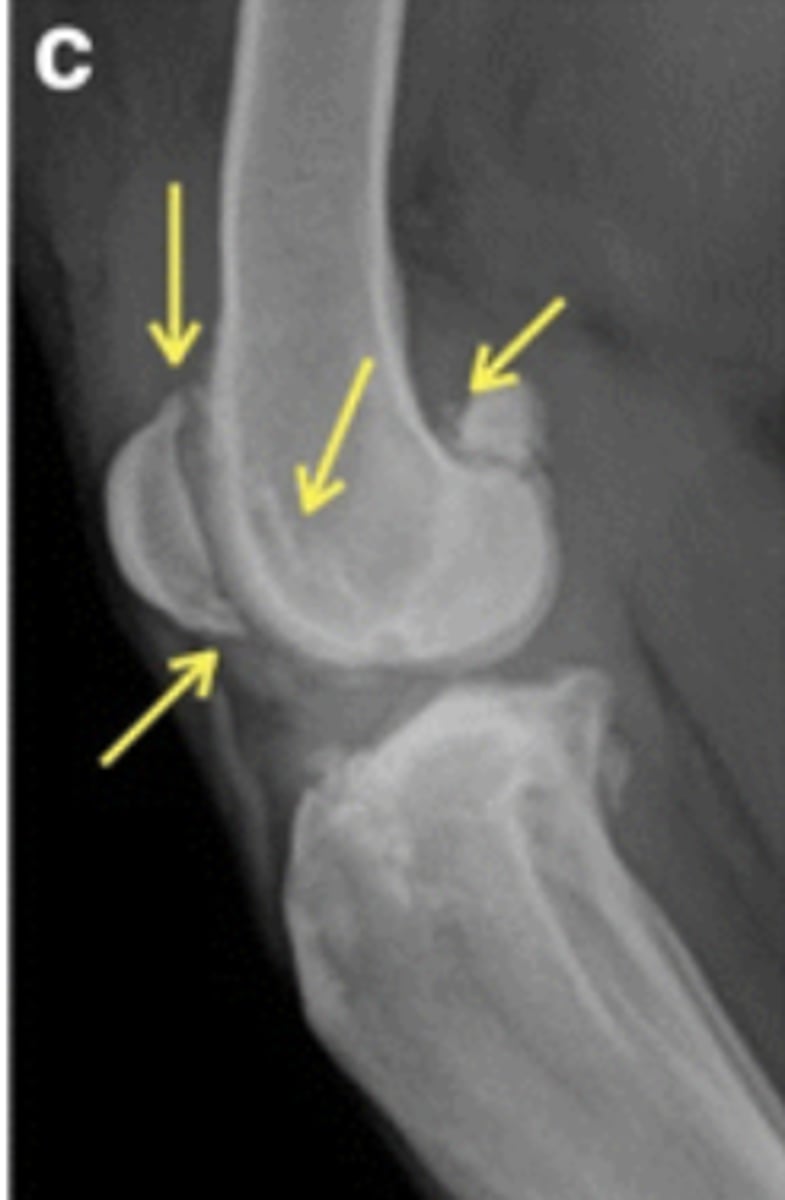

Dorsomedial

Where is this fragment located?

Type IV

Which Salter-Harris fracture is pictured?